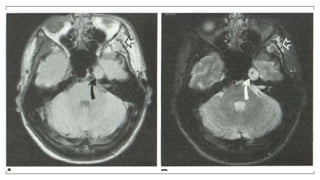

Cardiac Motion

Acquired without any form of motion compensation technique for cardiac motion, blurring

of the cardiac structures. The image on the right was obtained using cardiac gating. This

effectively eliminates cardiac motion.